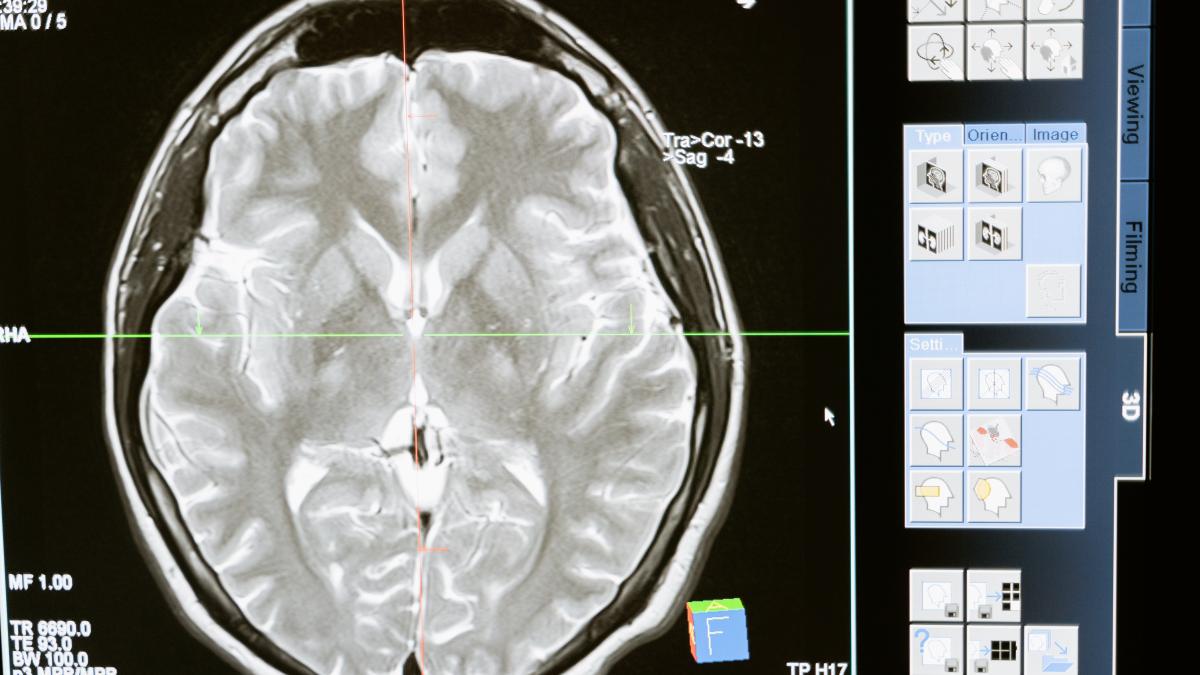

Valul cazurilor de demență diagnosticate greșit. Greșeala comisă de medici, demonstrată de un studiu

Un studiu recent sugerează că până la 13% dintre persoanele diagnosticate cu demență în Statele Unite ar putea fi, de fapt, diagnosticate greșit, suferind de o afecțiune care poate fi tratată. Cercetarea, condusă de facultatea de medicină a Universității Virginia Commonwealth (VCU) și Centrul Medical Richmond VA, explorează în detaliu legătura dintre demență și sănătatea ficatului.

Encefalopatia hepatică este o tulburare neurologică care poate apărea în urma unei afecțiuni hepatice severe, atunci când ficatul nu reușește să filtreze toxinele din sânge. Aceste toxine pot ajunge la creier, provocând tulburări cognitive similare celor observate în demență. Dr. Jasmohan Bajaj, hepatolog la VCU, subliniază importanța conștientizării acestei suprapuneri potențiale între demență și encefalopatia hepatică, care este tratabilă.